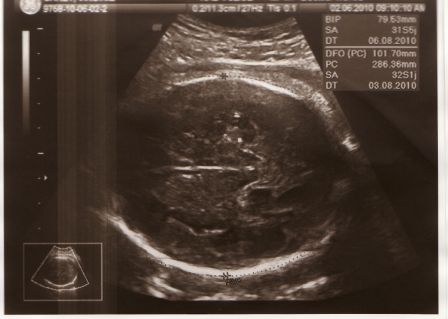

Bébé a désormais 7 mois. L'échographie - 02 juin - montre a nouveau que tout est normal. La petite puce fait maintenant 1,800 kg. Ceci est un poids normal à ce stade de la grossesse.

Bébé à 7 mois de grossesse

Par Virginie et Julien Garet le jeudi, juillet 1 2010, 18:00